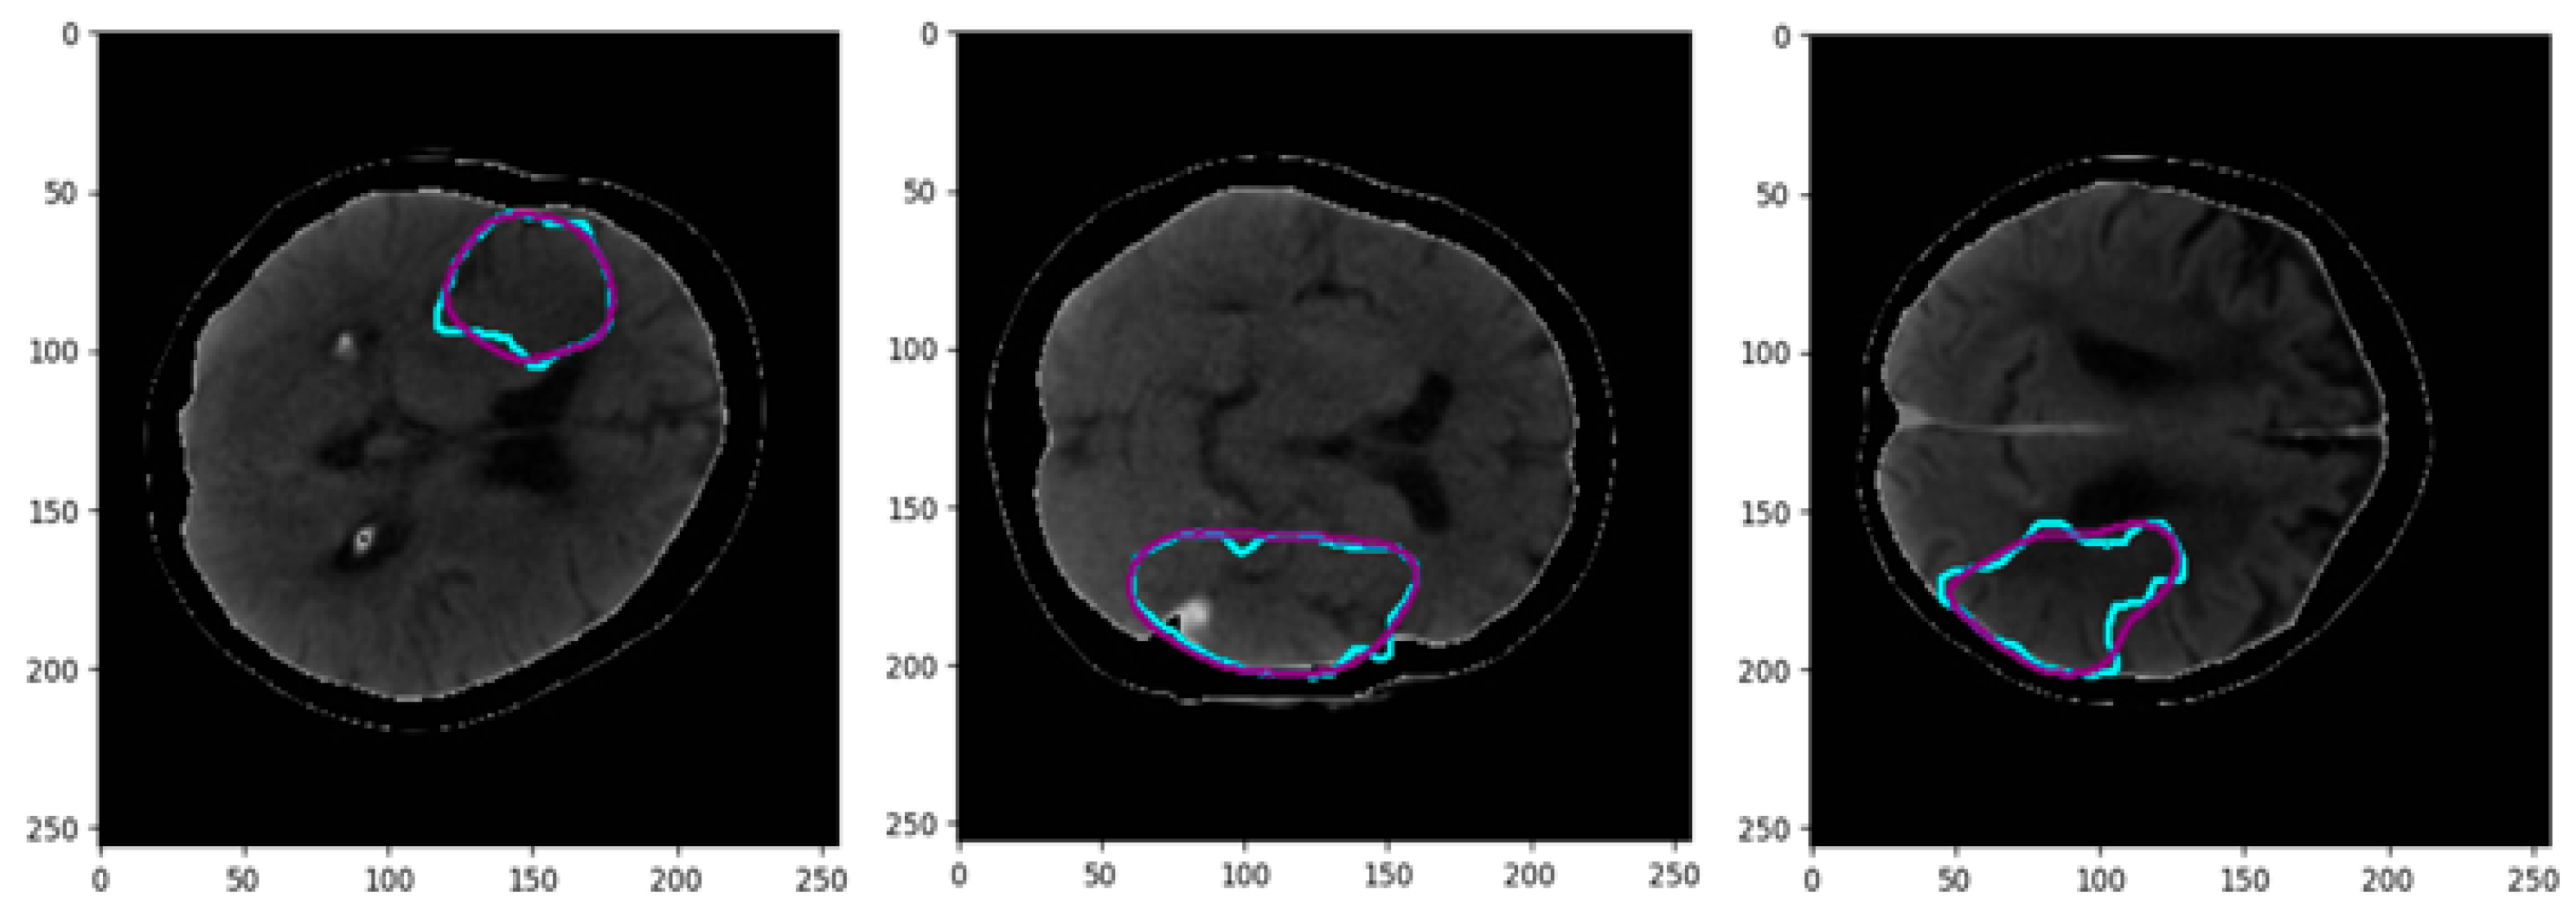

- The proposed network utilizes a channel of perfusion maps, including CBV, CBF, MTT, Tmax, and CT slice, to efficiently extract the stroke lesion.

3.1. Pre-Processing of Data

| [CBV, CBF, MTT, Tmax, CTSlice] | MultiresUNet | 76.52 | 73.09 | 75.12 | 71.19 |

| Ensemble Net | 86.61 | 84.13 | 84.98 | 77.67 | |

| CS-Ensemble Net | 92.43 | 90.14 | 91.66 | 86.16 |